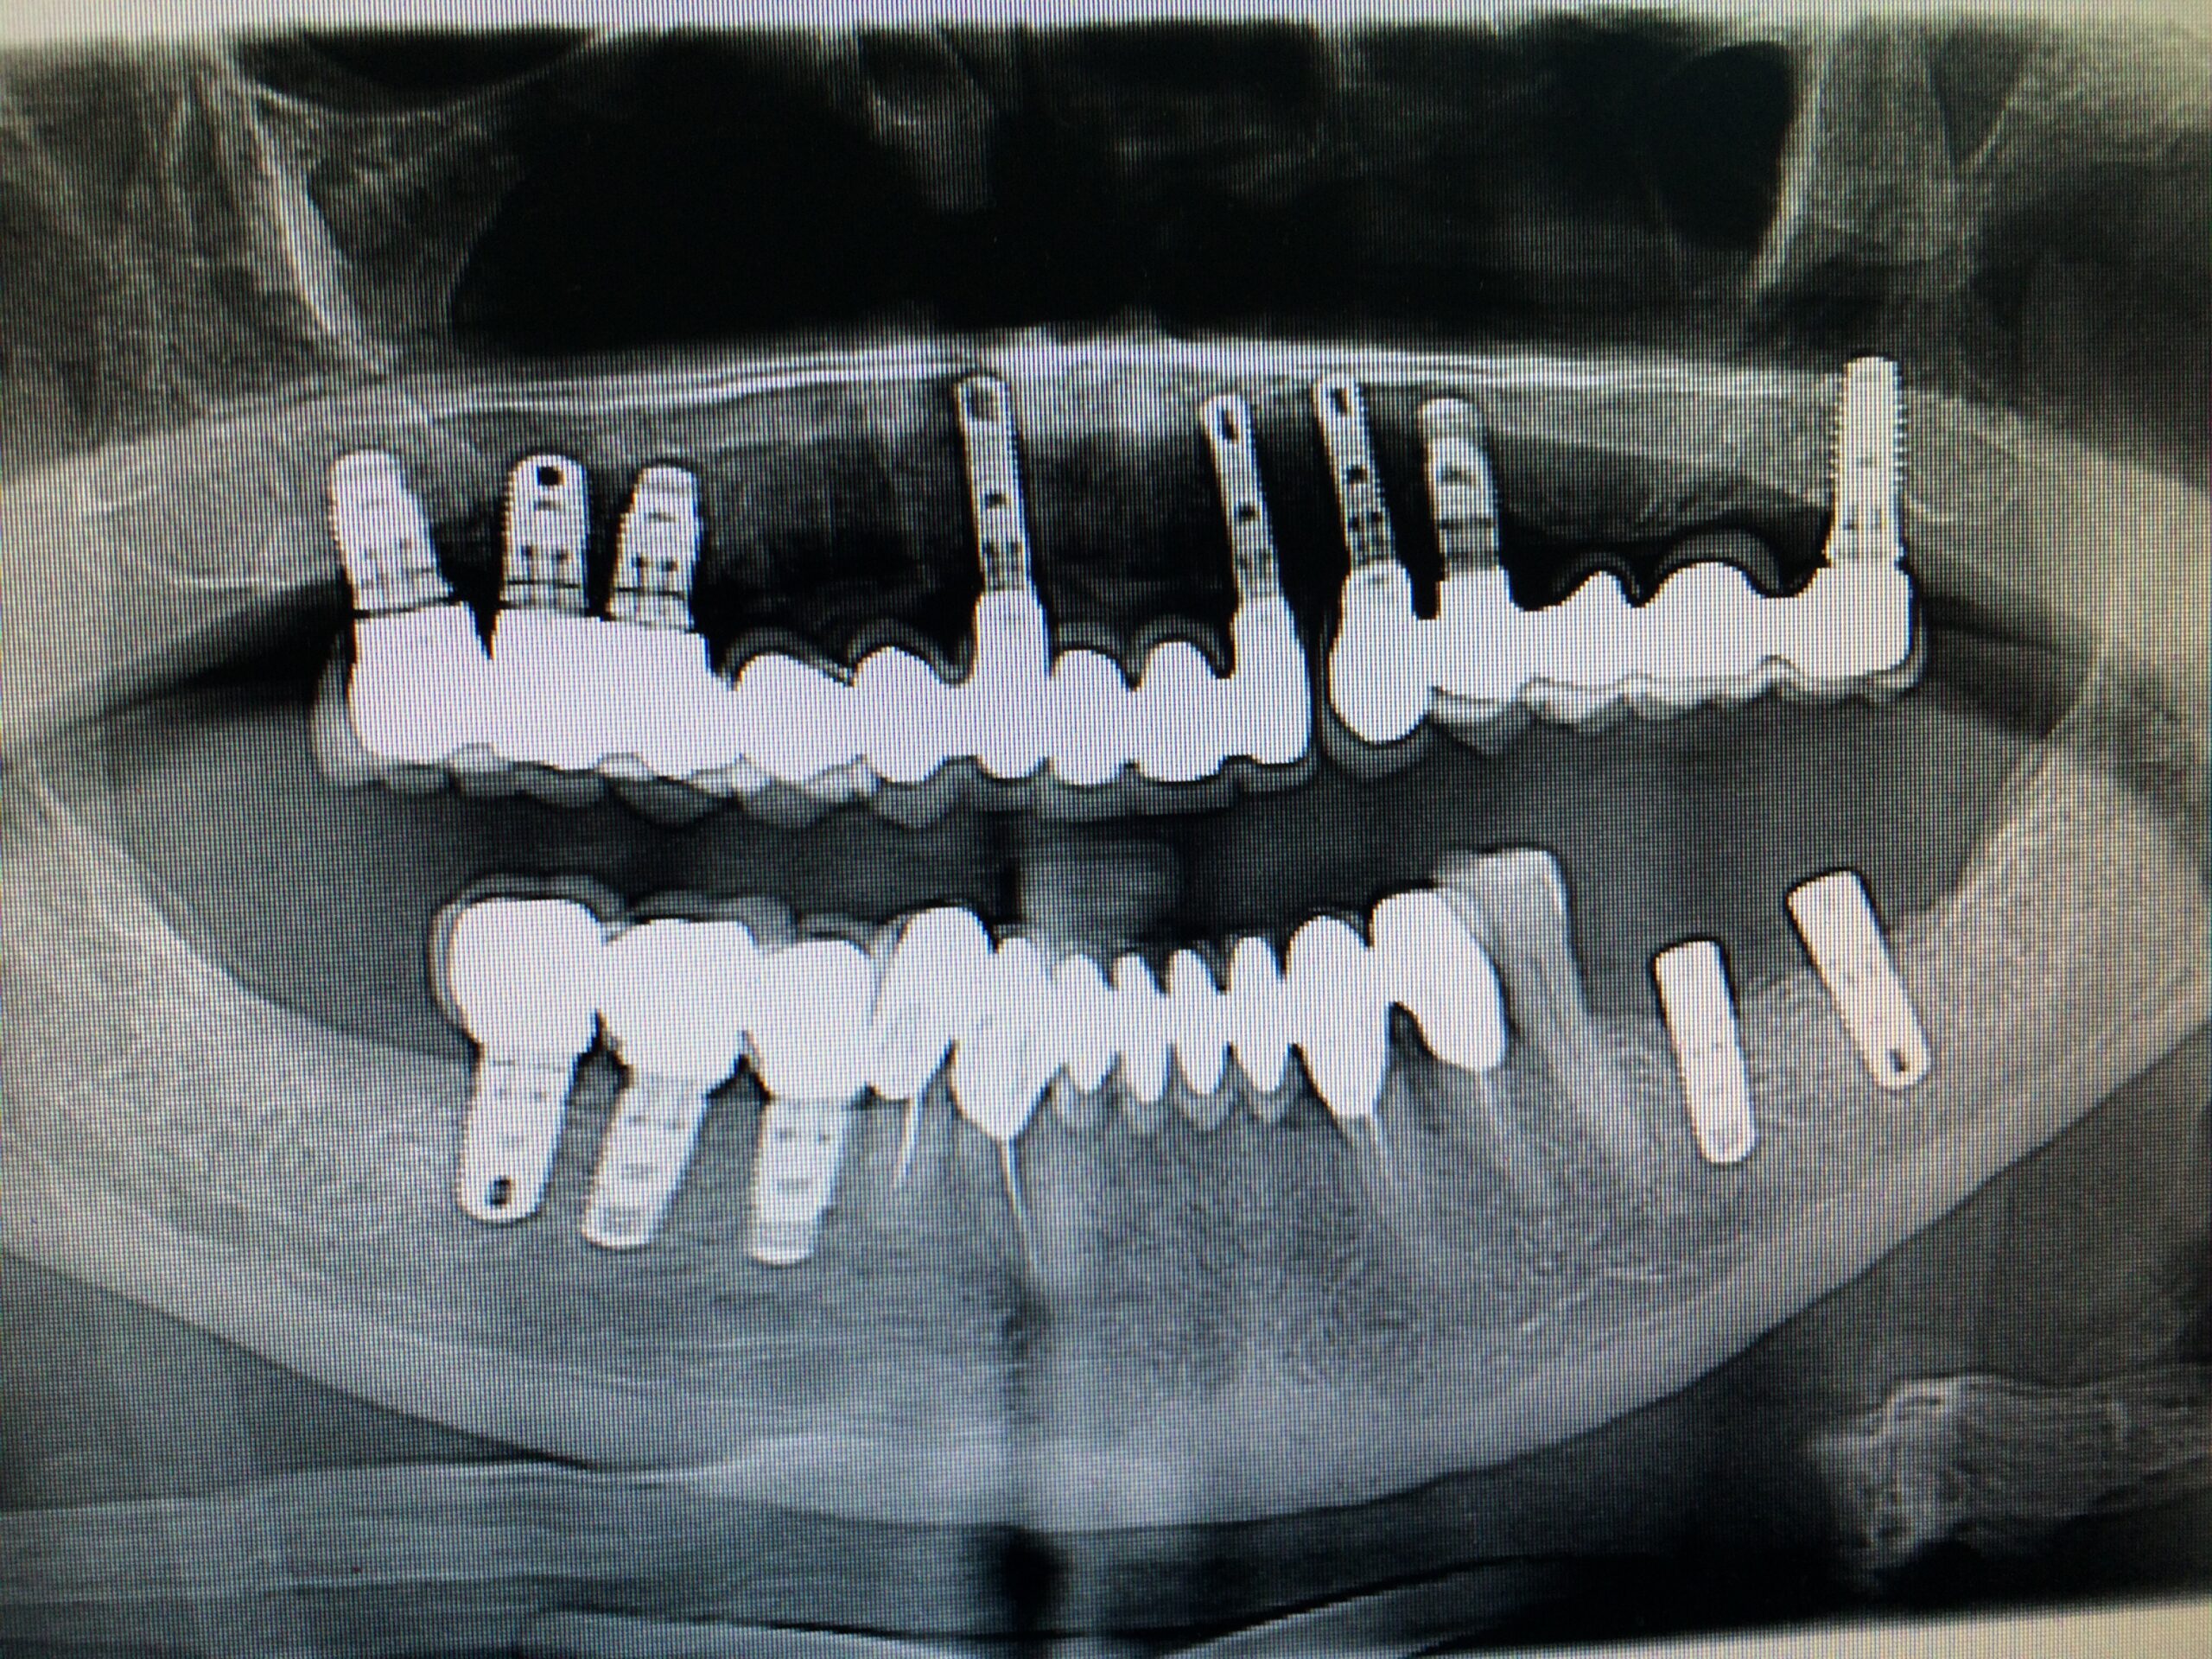

→ Pose du ou des implants

Durant cette étape, le praticien pose les implants dentaires pour remplacer les racines manquantes. À l’issue de cette intervention, vous sentirez des implants couverts par la gencive, et qu’ils sont mis en “nourrice” : cela permet à l’os de cicatriser autour des implants.

Ces dents provisoires sont placées afin de vous permettre de manger et de parler normalement en attendant la mise en place de la prothèse définitive.

→ Pose de la prothèse définitive

Après la cicatrisation de l’os et de la gencive, une simple prise d’empreinte comme sur une dent naturelle permettra la réalisation d’une prothèse naturelle et fonctionnelle.

- Implant unitaire

- Les implants encastrés

- La Réhabilitation implantaire totale

- Les implants distaux